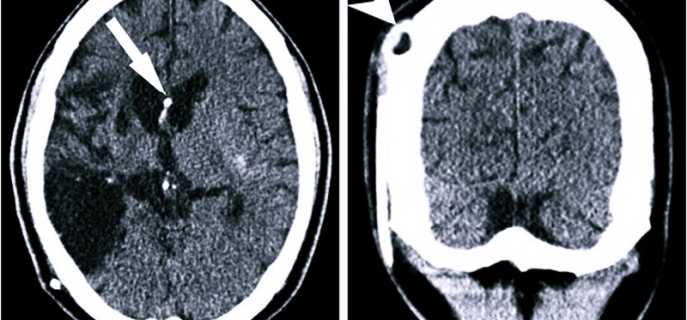

- Компьютерная томография (КТ) – послойное сканирование тканей, при котором визуализация происходит при помощи рентгеновских лучей. Методика обладает высокой разрешающей способностью и позволяет выявить мелкую псевдокисту, песок в полостных образованиях.

- Магнитно-резонансная томография (МРТ) – метод подразумевает послойное сканирование, при котором визуализация тканей осуществляется при помощи физического эффекта резонанса ядер в сильном магнитном поле. Исследование нельзя проводить при наличии металлических имплантатов у взрослого человека или ребенка.

Выбор методики исследования осуществляется лечащим врачом индивидуально. При помощи проведенной диагностики определяется характер образования (субэпендимальный тип, истинная киста), его локализация (справа или слева по отношению к срединной линии), а также размеры. Это дает возможность выбрать оптимальную терапевтическую тактику.